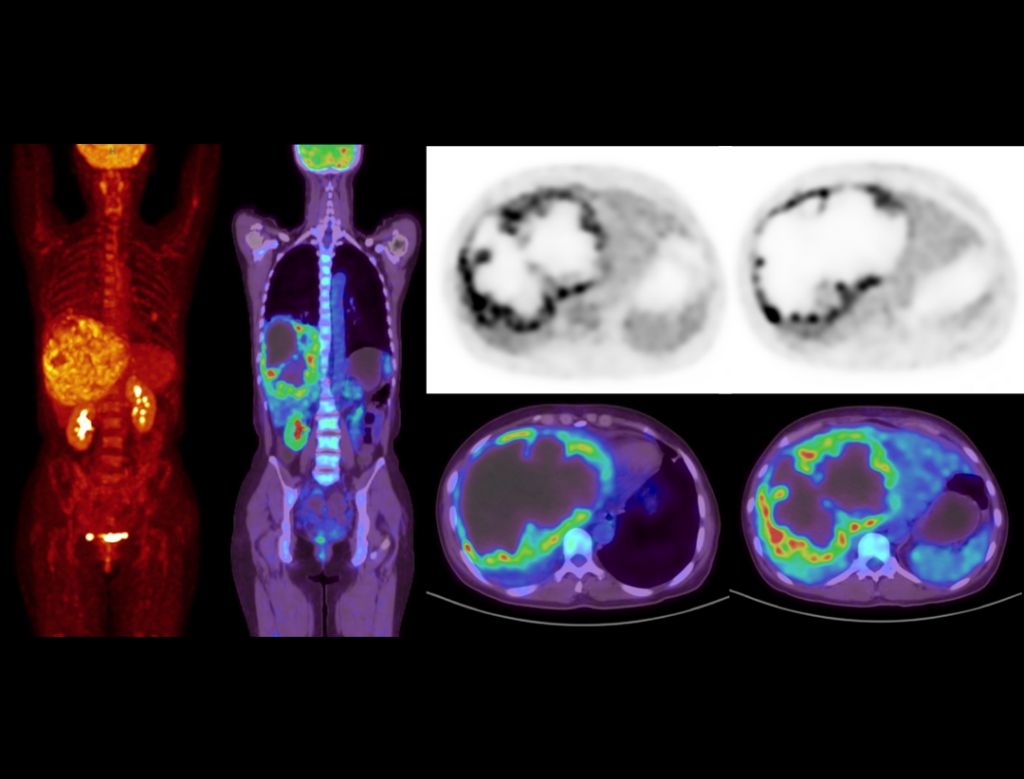

With the unique Integrated-Light-Guide Digital PET technology and a 160-slice CT system, uMI Vista combines high quality functional images with fine anatomical structure visualization. The state-of-the-art reconstruction technology and comprehensive applications further boost diagnostic precision in oncology, neurology and cardiology.

2.9mm NEMA Resolution

Outstanding resolution performance is achieved through systematic imaging chain engineering.

HYPER Iterative Reconstruction

Improves signal-to-noise ratio and contrast recovery to aid lesion detectability and quantitative accuracy.